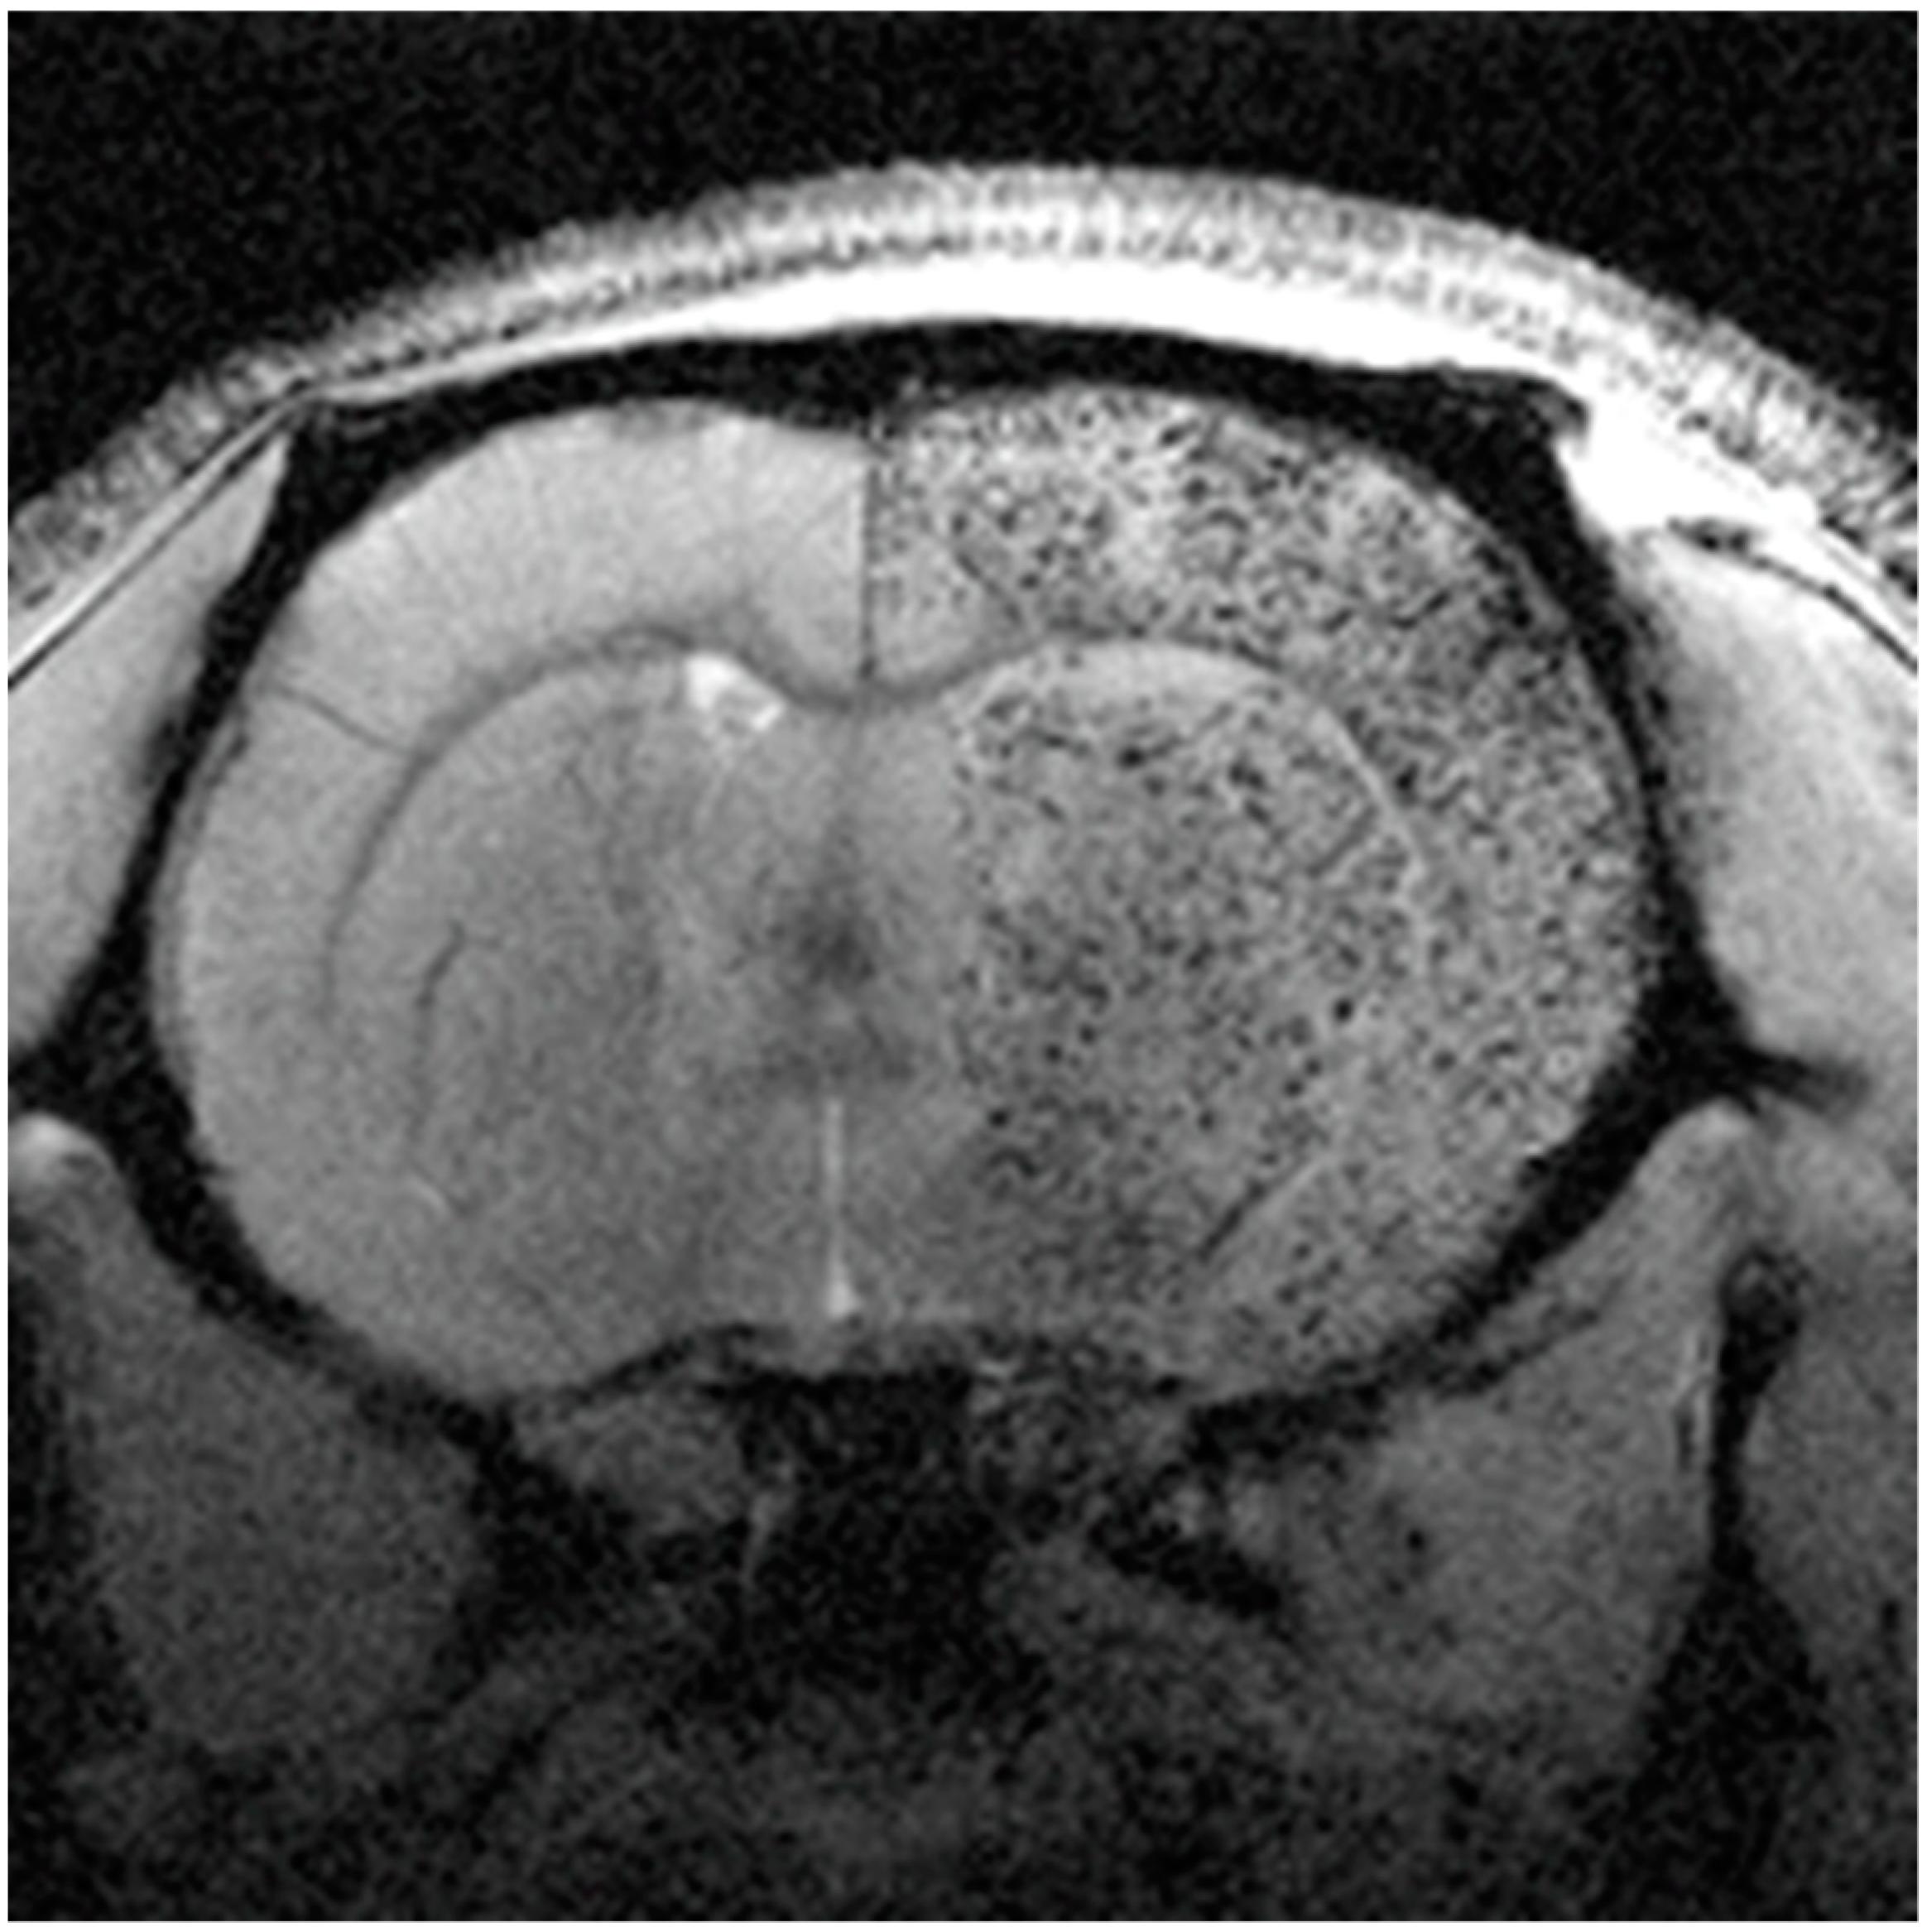

5.1. MRI Contrast Cell Agents

5.2. MNPs for MRI Cell Tracking in Stroke

- Argibay, B.; Trekker, J.; Himmelreich, U.; Beiras, A.; Topete, A.; Taboada, P.; Pérez-Mato, M.; Vieites-Prado, A.; Iglesias-Rey, R.; Rivas, J.; et al. Intraarterial route increases the risk of cerebral lesions after mesenchymal cell administration in animal model of ischemia. Sci. Rep. 2017, 7, 40758. [Google Scholar] [CrossRef]